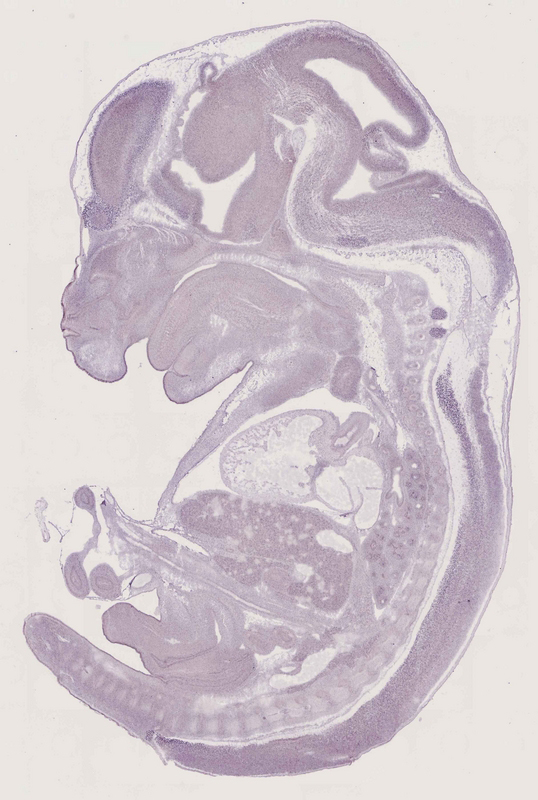

Specimen

euxassay_013785_05:

embryonic day 14.5

euxassay_013785_06: